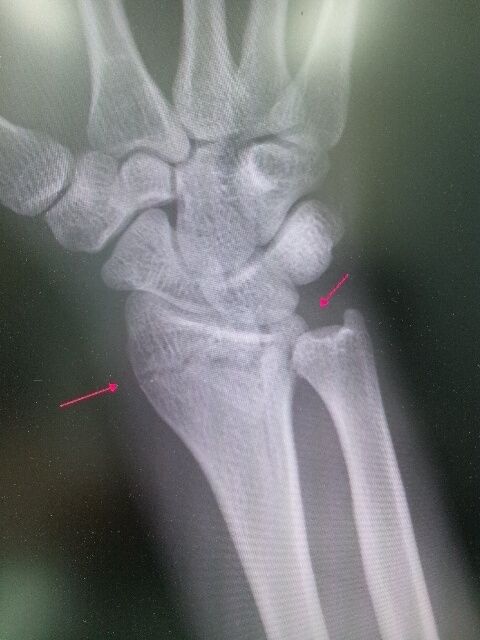

23歳男性 スノーボードで受傷

骨治療器、 持続低周波で 2週間で完全に骨癒合し 復帰!

2週間後